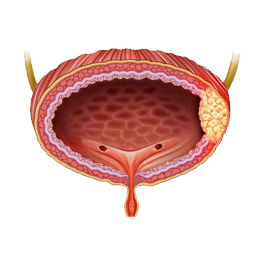

ΑρκΉΑ© «ΟΎΡρœΒΆ≥≥ΘΦϊΒΡΕώ–‘÷ΉΝω÷°“ΜΘ§ΖΔ≤Γ¬ ‘ΎΡ––‘÷–œ‘÷χΗΏ”Ύ≈°–‘Θ§ «ΟΎΡρœΒΆ≥÷ΉΝω÷–ΉνΈΣ≥ΘΦϊΒΡ“Μ÷÷ΓΘΑρκΉΑ©ΒΡ‘γΤΎΖΔœ÷ΚΆ÷ΈΝΤΕ‘ΜΦ’ΏΒΡ‘ΛΚσ÷ΝΙΊ÷Ί“ΣΓΘ